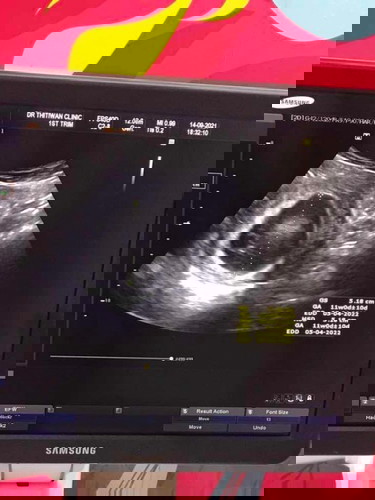

เราไปหาหมอมา3ที่แต่ละที่weekไม่ตรงกันเลยวันนี้ครบ11wยึดตามคลีนิคแรกคะหมอนัดอีกทีอาทิตย์หน้าครบ12wตอนนี้เครียดกังวลเสียใจมากแต่ไม่มีอาการปวดท้องหรือมีเลือดออกมีตกขาวมากขึ้นมีหน้ามืดบ้างเบื่ออาหารกินข้าวไม่ได้เลยและนมก็ยังคัดเต้ามากๆเลยคะ#ขอบคุณล่วงหน้านะคะ